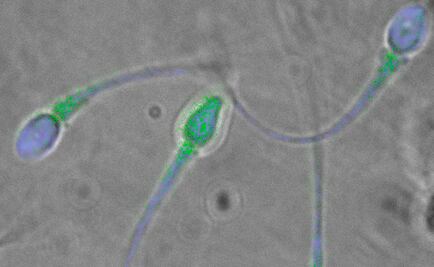

Las proteínas que permiten que el esperma del reptil se mueva y reconozca los óvulos son similares a las presentes en los humanos